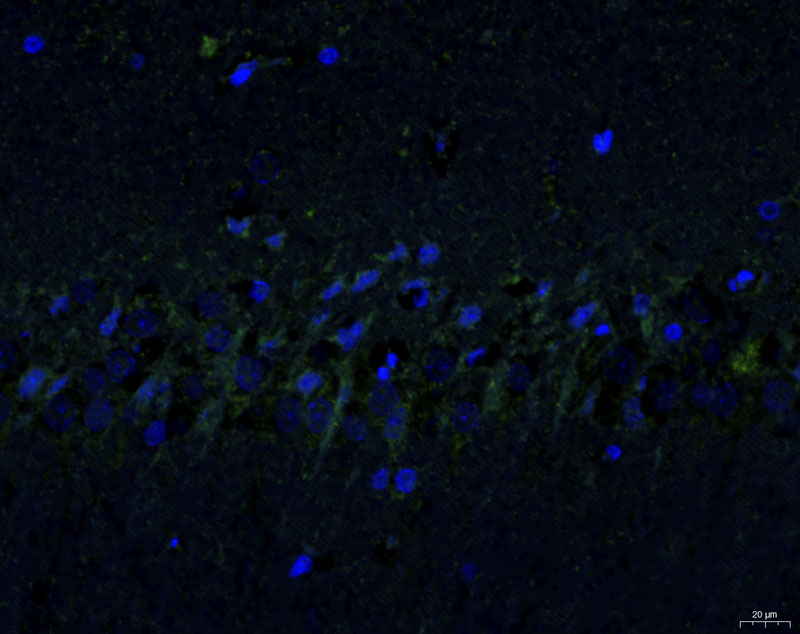

免疫熒光染色